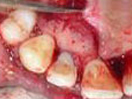

An Innovative Technique of saving a Tooth with Fracture Extending Sub-Gingivally (Chisel Type Fracture)

Tooth with Fracture Extending Sub-Gingivally

Showing picture line

Extending Palatally and

Sub-Gingivally.

Labial Soft Tissue

Reflected

Palatal Soft Tissue